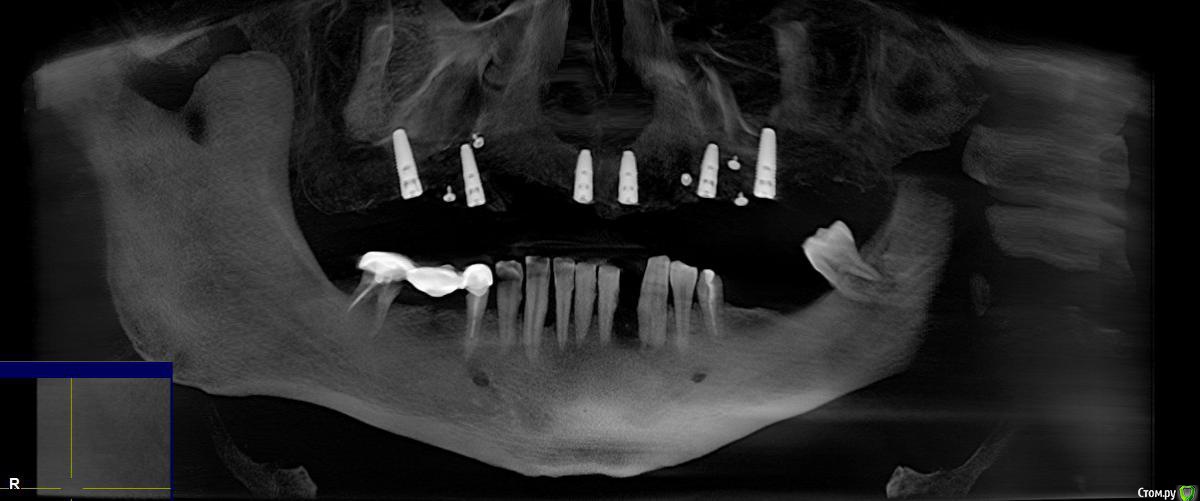

SaoNaum Опубликовано 18 ноября, 2017 Поделиться Опубликовано 18 ноября, 2017 (изменено) Прошу совета по плану восстановления нижнего ряда. Изменено 18 ноября, 2017 пользователем SaoNaum Ссылка на комментарий

колесников Опубликовано 18 ноября, 2017 Поделиться Опубликовано 18 ноября, 2017 Я бы предложил съемный с опорой на импланты. Не спешите говорить нет. Во первых нижние зубы практически все несостоятельны,подлежат удалению. Во вторых имеем дефицит тканей по высоте в некоторых участках. Если вы хотите несъёмную конструкцию на имплантах ,она будет включать искусственный базис скрывающий эти дефекты,но затруднительна будет гигиена. Конструкция без искусственной десны предполагает череду костных и мягкотканных пластик,что увеличивает стоимость и сроки. И самый главный момент-проприорецепция. Импланты не обладают такой чувствительностью как свои зубы,вам будет тяжело контролировать силу накусывания.На верхней челюсти у вас планируется несъёмная конструкция с опорой на импланты,предположу что из диоксида циркония. Очень прочная и практически бесчувственная конструкция. Если вам изготовят аналогичную конструкцию и на нижней челюсти,как минимум адаптация будет непростой,возможны сколы,дисфункция со стороны височнонижнечелюстного сустава. Конструкция дорогая и малоремонтопригодна. Совершенно обратная ситуация если у вас будет съемный низ. Протез изготовлен из более мягкого материала , «притирка» будет напоминать естестественное стирание эмали зубов,нагрузки на сустав меньше,гигиена проста,протез ремонтопригоден и стоит на порядок дешевле,базис протеза скроет все дефекты гребня. И последнее. Закончить работу стоит у того доктора ,у которого начали. 4 Ссылка на комментарий

red_butler Опубликовано 21 ноября, 2017 Поделиться Опубликовано 21 ноября, 2017 Здравствуйте, вопрос относительно совета, а какие зубы тогда нужно удалить с нижнего ряда?Спасибо.Я бы все убрал Ссылка на комментарий

колесников Опубликовано 22 ноября, 2017 Поделиться Опубликовано 22 ноября, 2017 Все удаляется Ссылка на комментарий